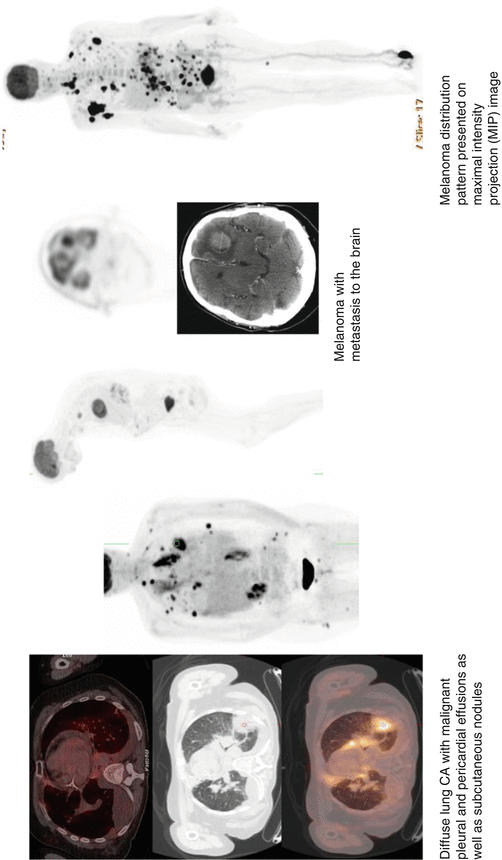

From www.researchgate.net

Overview of selected PET tracers used for monitoring of cancer therapy Fda Approved Pet Tracers Tauvid™, a radioactive diagnostic agent, has been approved by the fda for positron emission tomography (pet) imaging of the brain. Food and drug administration (fda) in 2020 for positron emission tomography. Tauvid has been approved by the u.s. Food and drug administration (fda) in 2020 for positron emission tomography (pet) imaging of adult patients with cognitive impairments. Food and drug. Fda Approved Pet Tracers.